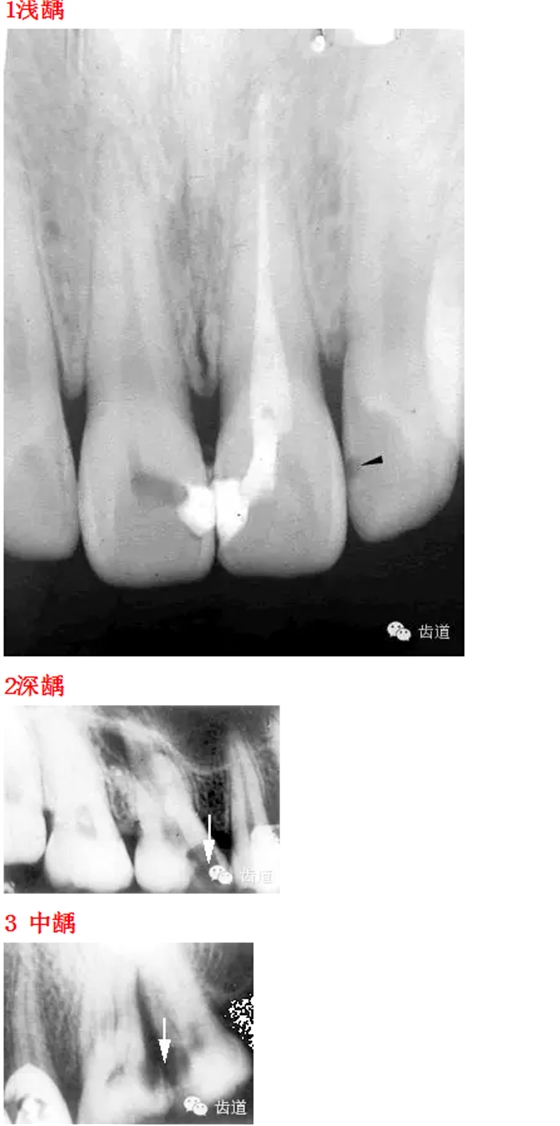

首頁(yè)口腔影像 26種口腔病變X光片

26種口腔病變X光片